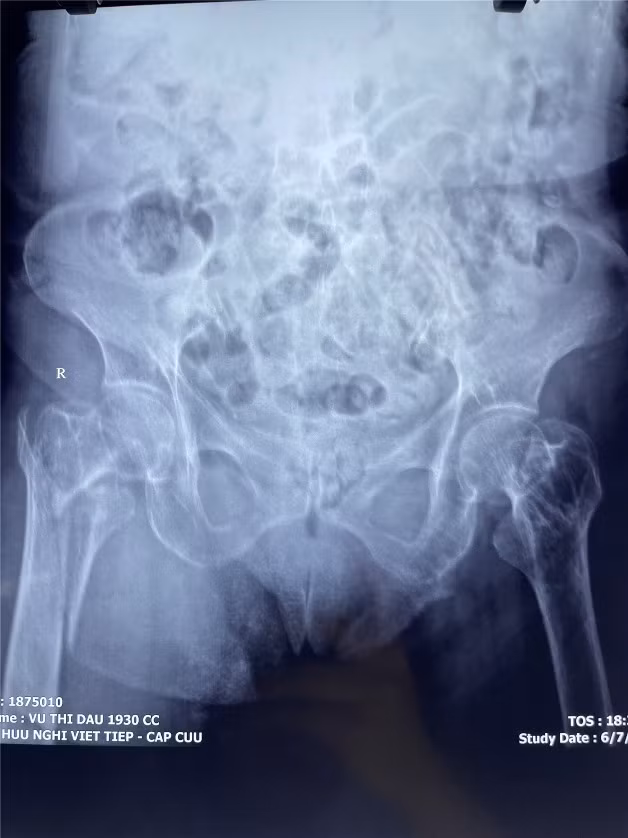

![]() |

| Gãy khối máu chuyển xương đùi của người bệnh trước phẫu thuật |